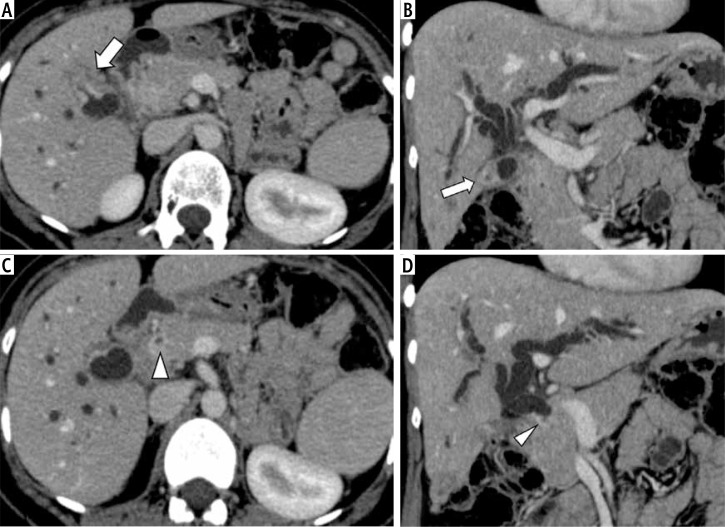

Material and methods: This retrospective study screened cross-sectional imaging (contrast-enhanced computed tomography [CT] or magnetic resonance imaging [MRI]) of consecutive patients with histopathological or cytological diagnoses of GBC. The CT/MRI images of patients with multifocal disease (defined as the presence of two or more foci of abnormal wall thickening, intraluminal polypoidal lesions or masses in the gallbladder, cystic duct, or the extrahepatic bile ducts with the intervening area of normal gallbladder/extrahepatic bile ducts) were evaluated by two radiologists independently for various imaging findings.

Results: Of the 324 patients, 17 (5.2%; 13 females; mean age, 54 ±11 years) had multifocal disease with two sites of involvement in all cases. The most common sites of involvement were the gallbladder fundus and neck region (58.8% of cases), followed by the gallbladder fundus and common bile duct (29.4%). Wall thickening type of GBC was the most common morphological subtype (85.3%), followed by mass forming type (14.7%). The majority (70.6%) of cases showed the same morphology at both sites, while 29.4% showed different morphology. Most (70.6%) of the patients with multifocal GBC were unresectable at the time of diagnosis.